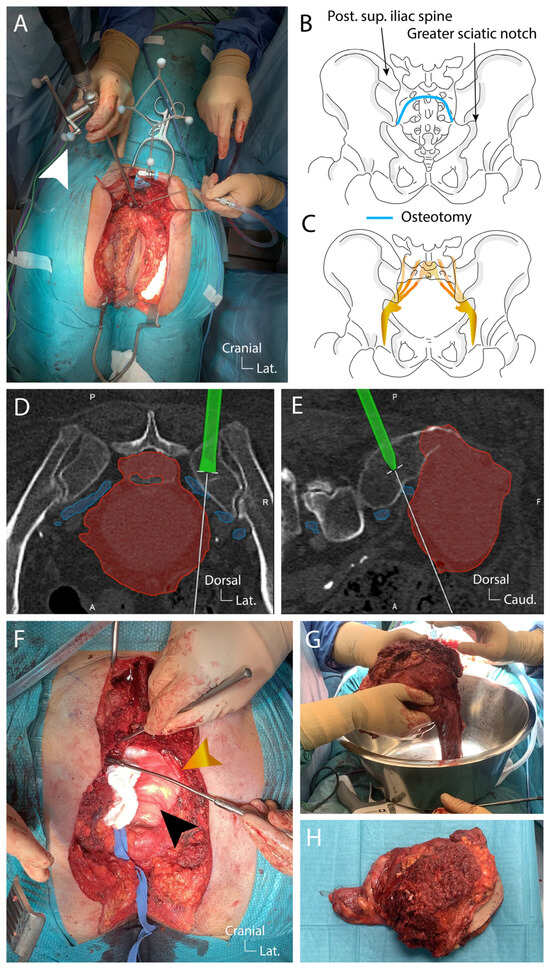

4.3. Surgical Technique